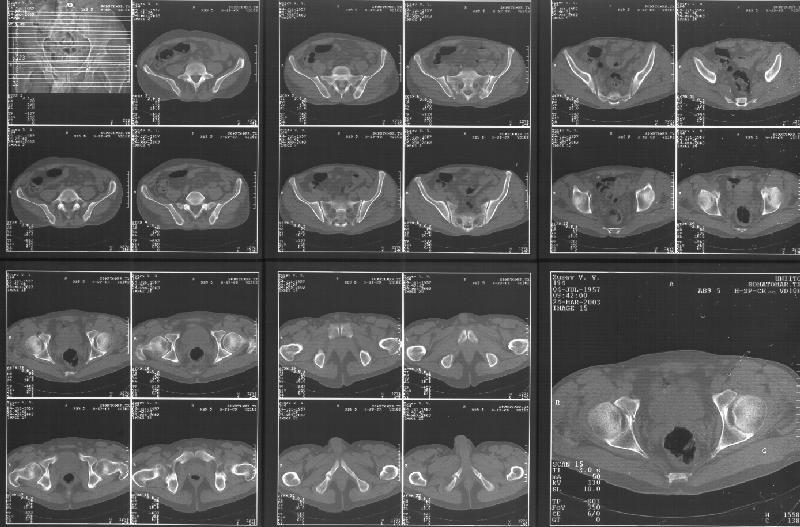

ФасInlet

Based on the CT images you provided, he appears to have a nonunion of the the right ischium, which would explain his symptoms. General principles of treatment of hypertrophic (which this appears to be) nonunions suggest rigid fixation, but I'm not sure what the best approach would be. Could get a lag screw across the fracture through a Kocher-Langenbeck approach or plate osteosynthesis through direct ischial approach, but perhaps Chip, Adam or someone with more pelvic fracture experience could enlighten us all.

I think this is just a pelvic ring disruption that has gone on to a non-union. The arrow is pointing to the inferior ramus non-union, and

the sup ramus is a high "root" fracture, right near the pecten. The sup ramus fracture enters the tab - you could call it an acetabular

fracture - but down here in Dallas we treat these acutely as stable pelvic ring injuries. The fracture in the anterior portion of the

acetabulum is so low it doesn't seem to cause much trouble.

His R sacroiliac joint is opened anteriorly a little bit - the "unreduced posterior lesion" Alex mentioned in his first post. My earlier post about plating, bone grafting, etc., is all wrong.

What you have is a pelvic fracture that hasn't healed after 4 months or so, with a minimal deformity.

I think what I would offer the guy is a percutaneous iliosacral screw to stabilize and improve the SI joint alignment, coupled with a perc anterior column screw to stabilize the high ramus fx. These screws aren't easy to place, and have a host of potential problems and complications. But, I think they would work.

Речь идёт о коплексном двустороннем повреждении таза с нарушением тазового кольца.

А именно: разрыв илио-сакрального сочленения справа, на этой же стороне трансацетабулярный перелом с незначительным смещением, перелом подвздошной кости слева. Исходя из вышеперечисленного, меня не удивляют двусторонние жалобы пациента. Однако, учитывая представленные снимки ЯМР и времени, прошедшим с момента травмы мне представляется пока преждевременным говорить об образовании ложных суставов. Судя по развиввшейся костной мозоли в области вышеперечисленных очагов, все переломы находяться в стадии консолидации. Вполне возможно, однако, что трансацетабулярный перелом приведёт в дальнейшем к развитию посттравматического артроза ТБ- сустава.

Поэтому тактику лечения я бы выбрал консервативную. Через 6 Месяцев ЯМР можно повторить. Не думаю, что транскутанная фиксация винтами приведёт к облегчению болей пациента. При подобной ситуации (см. выше) боли могут сохраняться до года.